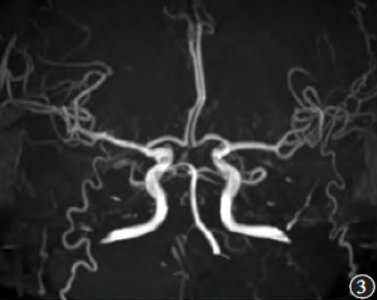

影像学检查:头颅MRI及MRA(图1~3)示双侧丘脑及左侧小脑半球多发斑片样T1WI低信号影、T2WI高信号影,T2WIFLAIR呈高信号,DWI信号随b值升高并增高,ADC呈低信号。DSA(图4)示Percheron动脉起源于左侧大脑后动脉P1段近段,右侧丘脑穿通动脉分支显影纤细,左侧丘脑穿通动脉分支血流缓慢。

图3MRA未见明显异常